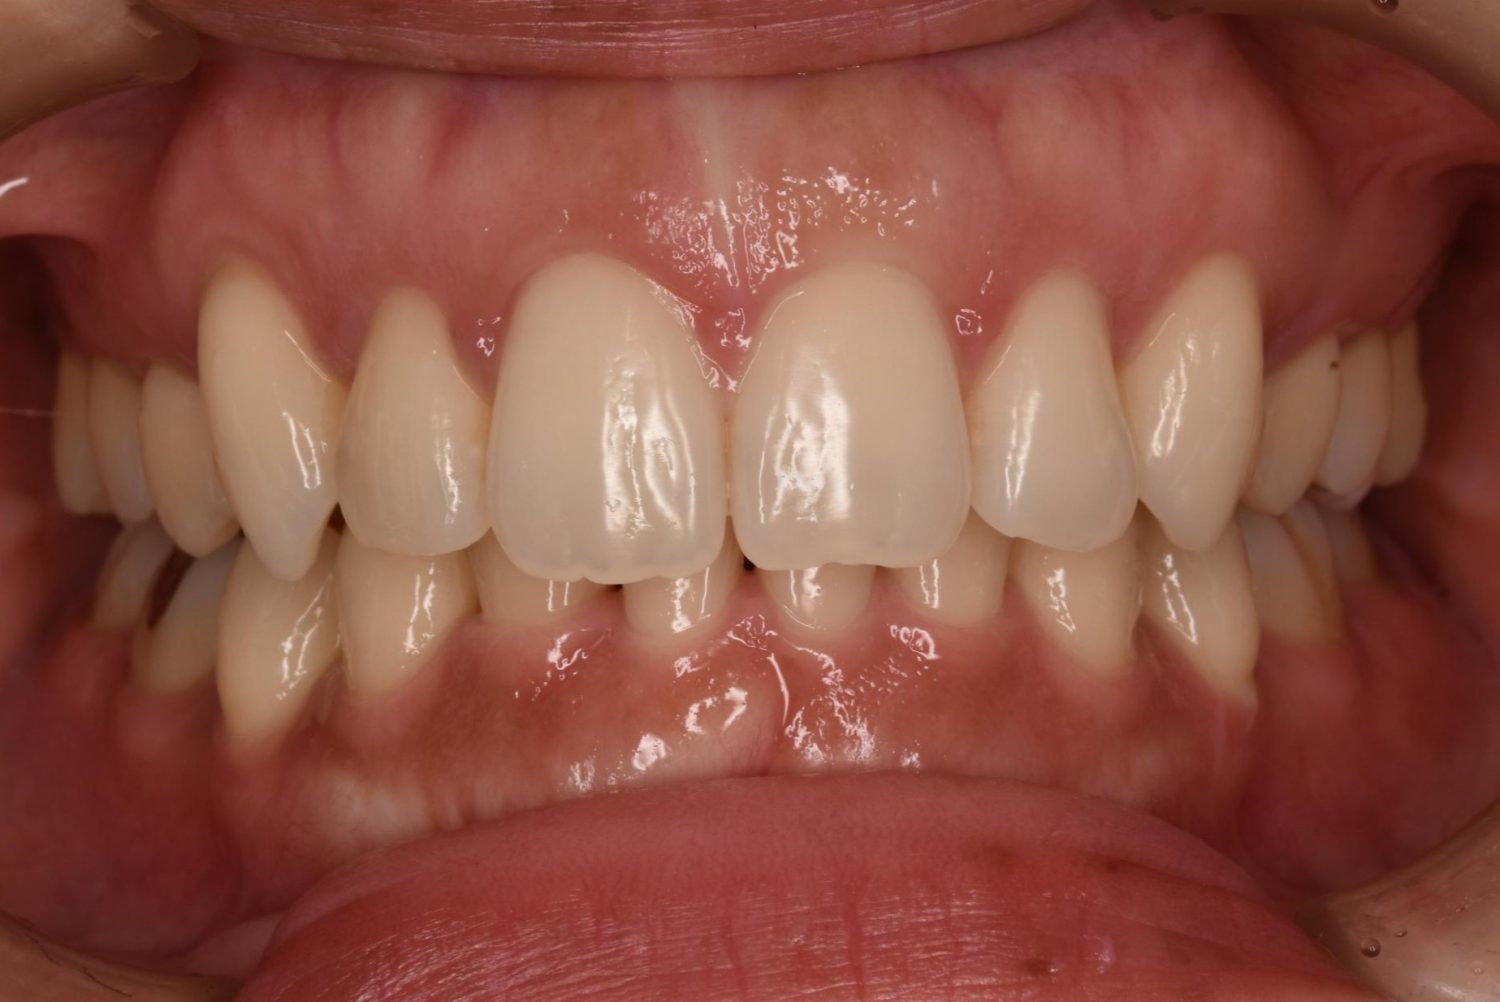

| 主訴 | 20代女性の患者さん。右上の八重歯が突出しており、前歯の見た目にコンプレックスを抱いていた。下顎の左右第2小臼歯(5番)が舌側に大きく傾斜しており、食事の際に、食べかすが詰まりやすく日常的に不快感を覚えていた。噛み合わせの改善と、見た目のバランスを整えたいという希望があり、矯正治療を行うことになった。また、目立ちにくい方法で治療を進めたいという意向から、マウスピース型装置の矯正 “インビザライン”を希望。 |

| 治療内容 | 下顎の左右第2小臼歯(5番)は舌側に大きく傾斜しており、矯正治療における歯の移動効率や全体の歯列バランスを考慮し、便宜抜歯を行った。また、上顎の左右第1小臼歯(4番)についてもスペース確保の目的で抜歯を実施し、全顎的な歯列の配列を円滑に進められるよう計画。矯正装置は、患者さんのなるべく目立ちにくい治療を行いたいという強い希望とライフスタイルに合わせて、マウスピース型矯正装置「インビザライン」(※1)を採用。抜歯が必要となる矯正治療は、診断・治療の難易度が高い方法である。当院ではCTやセファログラムなどの先進的な設備を完備し、多角的な診査診断と豊富な臨床経験をもつ理事長による治療を行うことで、このような難症例にも対応可能。 また、当院は矯正治療だけでなく、むし歯治療やクリーニングなどの一般歯科・予防治療も一貫して管理する包括的な審美治療を行う総合クリニック。治療中にむし歯などの問題が見つかっても、すぐに対応できるため、患者さんの通院の負担をできる限り抑えたスムーズな対応が可能。矯正専門医院ではできない包括的なサポート体制こそが、シャングリラデンタル横浜歯科矯正歯科で矯正治療を受けるメリットである。 矯正治療中は定期検診で経過の確認とクリーニングを行い、必要に応じて治療計画の見直しやマウスピース型装置の追加を行った。患者さんの高い装着遵守率も相まって、歯列は順調に整い、機能的にも審美的にも良好な結果をえることができた。 (※1)未承認医薬品等であるため医薬品副作用被害救済制度の対象とはならない可能性があります。 |